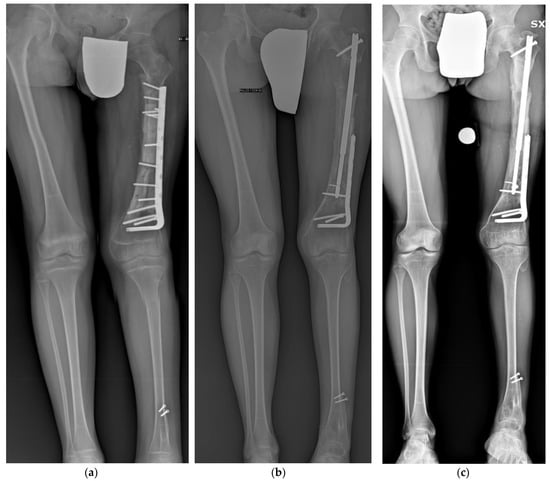

| Tibia | 11/F | Proximal tibia composite prosthesis for OS | 30 | 40 | 10 | Yes |

| Femur (A) | 19/F | Proximal tibia composite prosthesis for OS | 40 | 30 | 10 | Yes |

| Tibia | 25/M | Proximal tibia composite prosthesis for ES | 100 | 80 | 30 | Yes |